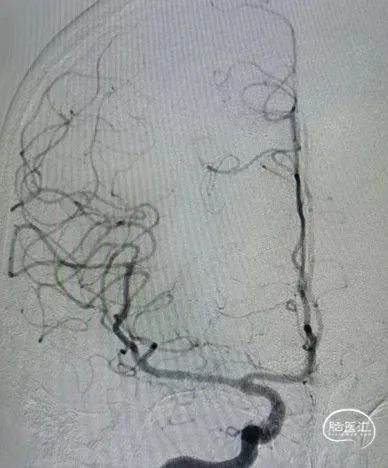

6F-远端通路导管在黑泥鳅导丝的指引下通过闭塞段送至眼动脉段,造影证实闭塞段在海绵窦段,予以ADPAT技术取出少量血栓,仍未开通。

通过微导管释放取栓支架,SWIM取栓技术,可见海绵窦段狭窄,前向血流不稳定。

利用PTA球囊导管对狭窄处进行扩张,可见狭窄明显改善,但眼动脉段以后闭塞,再次将取栓支架予以取栓,可见斑块逃逸至M1段。

多次利用取栓支架SWIM技术对逃逸斑块进行取栓但未成功。

利用赛诺神畅 NOVA DES®颅内药物洗脱支架锚定后释放,血管再通,mTICI 3级,局部动脉给药替罗非班(0.2ug/kg.min)约3ml,持续15分钟。静脉(0.1ug/kg.min)持续泵入24小时后改为口服双抗。